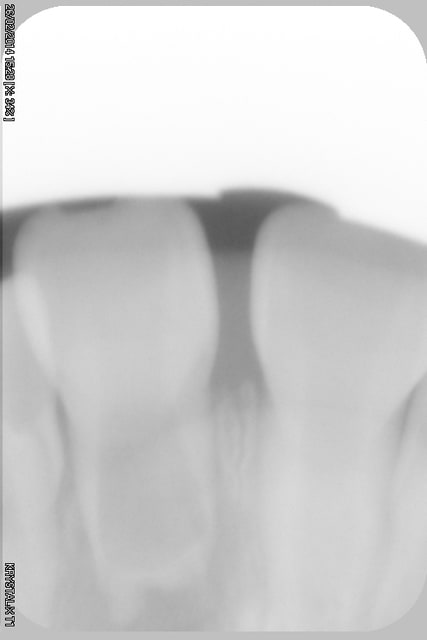

- radios en pièce jointe

- Déterminer par cone beam l'intégrité des parois radiculaires (Y-a-t-il une communication endo paro ou non?)

- Essayer de conserver ce qui reste de la racine par un ttt CaOH ou obturation radiculaire à la biodentine ou au MTA blanc?

- stopper ce qui est vraisemblablement une résorption inflammatoire (faut pas trainer!)

Les objectifs à moyen/long terme, au choix :

- Implant en 21

- Fermeture d'espace et implant plus en postérieur (étape ortho plus complexe, mais évolution sur le long terme meilleure si l'implant n'est pas en 21 mais en 24 par exemple)

- Soyons fous, si la nécessité d'extraction de prémolaires se présentait, pourquoi pas tenter une auto-transplantation? Les résultats semblent meilleurs avec des prémolaires immatures.